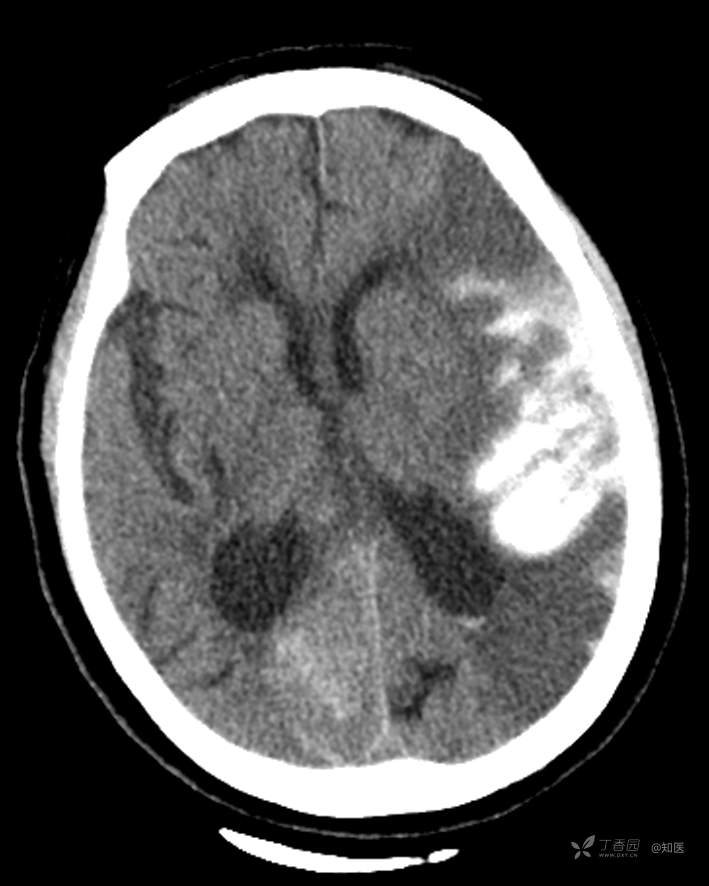

4-22日查房患者呈昏睡状,混合性失语,右侧肢体肌力障碍较入院时加重,胃肠减压引流物为深黄绿色液体,量约150ml。查体:GCS 9分(睁眼反应 3分+语言 1分+运动 5分),NHISS评分23分(意识水平 2分+提问 2分+指令 1分+凝视 2分+面瘫2+左上肢 1分+右上肢4分+左下肢 2分+右下肢4分+语言 3分),昏睡状,查体欠合作,混合性失语,粗测智能查体不配合。双眼闭目紧,双侧球结膜水肿,双侧瞳孔等大等圆,直径约4.0mm,对光反射灵敏,眼球无自主运动,无眼震,右侧鼻唇沟浅,口角向左歪斜。咽部查体不配合。转颈、耸肩查体不配合。伸舌不配合。右上肢肌力1级,右下肢肌力2级,左上肢肌力3级,左下肢肌力4级,四肢肌张力减低。四肢深浅感觉及共济运动查体不配合。右侧巴氏征阳性,左侧巴氏征阴性。颈抵抗。双侧布氏征及克氏征均阴性。辅助检查:头颅+胸部CT:与前片(2021-4-21 13:57)对比,现片示:1、环池、桥前池及大脑镰后部及小脑幕高密度影,考虑出血,较前新发。2、额颞顶叶高低混杂密度影,考虑梗塞伴造影剂残留;左侧大脑中动脉走行区致密影,系术后改变;请结合临床。3、多发腔梗,脑白质脱髓鞘,脑萎缩。4、双肺间质性改变,双肺下叶纤维索条,双侧胸腔微少量积液征象,双侧胸膜增厚。5、主动脉及冠状动脉管壁多发钙化斑块。三线主任医师、二线主治医师查房后示:根据患者病史、体征及辅助检查,目前诊断:1.脑梗死出血转化;2.左侧大脑中动脉次全闭塞;3.左侧大脑中动脉支架植入术后;4.高血压2级(很高危);5.2型糖尿病;6.应激性溃疡伴出血。目前病情及治疗上需注意以下问题:1.患者出血转化,增加脱水剂剂量,调整为20%甘露醇 125ml 每8小时一次、甘油果糖 250ml 每12小时一次,同时结合患者球结膜水肿,白蛋白正常低值,今日给予补充人血白蛋白10g,注意监测电解质等变化。2.患者为蛛网膜下腔出血,给予泵入尼莫地平预防脑血管痉挛。3.患者左侧大脑半球见大片脑白质脱髓鞘,考虑脑白质营养不良,给予维生素B1、维生素B12、维生素C、维生素B6及依达拉奉改善微血管通透性;4.患者出现应激性溃疡伴出血,今日暂禁食,给予泮托拉唑抑酸及肠外营养补充,密切观察消化道出血情况,根据病情变化调整抑酸药物剂量及频次;5.患者卧床,今晨见明显痰多,给予化痰等对症处理,监测血常规及脓毒症2项指标。6.向家属再次告知病情,因患者高龄、既往高血压及糖尿病病史,此次治疗出现出血转化,存在意识障碍加深、病情加重可能。7.密切观察神经系统体征变化。遵嘱执行。

4-23日查房:患者呈中度醒状昏迷,右侧肢体肌力障碍较入院时加重,胃肠减压引流物为黄绿色液体,量约200ml。入院后至今晨入量为4050ml,出量为4850ml。查体:GCS 6分(睁眼反应 2分+语言 1分+运动 3分),NHISS评分35分(意识水平 3分+提问 2分+指令 2分+面瘫3分+左上肢 4分+右上肢4分+左下肢 4分+右下肢4分+感觉 2分+语言 3分+构音障碍 2分+忽视 2分)。中度昏迷。双目睁眼状,双侧球结膜水肿较昨日明显,双侧瞳孔等圆,不等大,右侧直径约3.5mm,左侧瞳孔直径约3.0mm,对光反射灵敏,眼球无自主运动,无眼震。右侧鼻唇沟浅,口角向左歪斜。咽部查体不配合。转颈、耸肩查体不配合。伸舌不配合。四肢肌力检查不配合,右上肢落鞭征阳性,左上肢落鞭征阴性,右下肢不能撑于床面,左下肢可撑于床面,四肢肌张力减低。四肢深浅感觉及共济运动查体不配合。右侧巴氏征阳性,左侧巴氏征阴性。颈抵抗。双侧布氏征及克氏征均阴性。辅助检查:经颅多普勒示:左侧大脑中动脉峰值流速极低,右侧大脑中动脉及双侧大脑前动脉血流速度未见明显异常。头颅CT(2021-04-22):与前片(2021-4-21)对比,现片示:1.环池、桥前池及大脑镰后部及小脑幕高密度影,较前减少。2.额颞顶叶高低混杂密度影,考虑梗塞伴造影剂残留;左侧大脑中动脉走行区致密影,系术后改变;基本同前。请结合临床。3.多发腔梗,脑白质脱髓鞘,脑萎缩。同前。二线主治医师查房后示:患者目前诊断明确。现治疗上需注意以下问题:1.患者夜间体温上升,最高38度,结合患者卧床、痰多、不易咳出,且化验检查提示炎性指标较前明显升高,今日给予头孢哌酮舒巴坦抗感染治疗,同时继续雾化祛痰等。2.因患者应激性溃疡并出血,昨日查胃液潜血阳性,但经给予泮托拉唑抑酸护胃治疗后消化道出血未进行性加重,胃管引流物为黄绿色液体,今日暂继续给予氨基酸、脂肪乳等肠外营养支持,安排再次复查胃液潜血,若转阴可给予肠内营养加强支持治疗。3.患者血压仍有偏高,夜间泵入乌拉地尔控制,今日给予左氨氯地平平稳控制血压,监测血压变化。4.患者昨日血糖波动在6.8-11.4mmol/l,结合其糖化血红蛋白为6.4%,暂不干预血糖,继续监测血糖变化。5.患者意识障碍程度加重,双侧瞳孔不等大,但光反射灵敏,考虑与脑梗死后水肿高峰有关,治疗上继续加强脱水,向家属再次详细告知病情及目前诊疗方案,存在颅内压增高至脑疝形成、呼吸心跳骤停可能,表示理解知情。密切观察生命体征及神经系统体征变化。遵嘱执行。